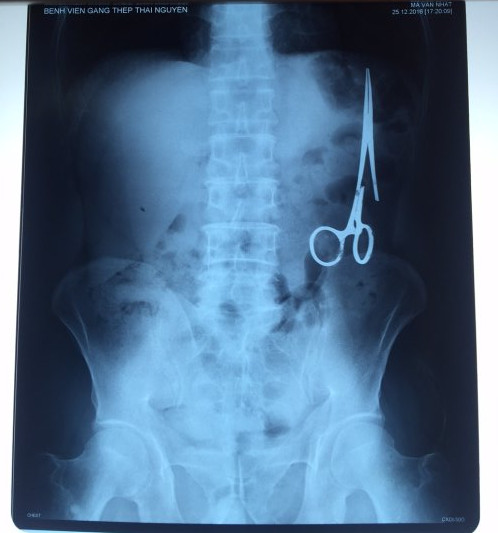

遺留在病人腹中的剪刀

據(jù)越南青年報1月2日報道,在越南首都河內醫(yī)療專家的幫助下,越南東北部的太原?。═hai Nguyen)鑄鋼醫(yī)院的醫(yī)生日前從54歲患者M.V.N腹中取出一把醫(yī)用剪刀。這把剪刀是此前曾為M.V.N手術的醫(yī)生遺留的,已經(jīng)在其腹中待了18年時間。

醫(yī)務人員表示,這把剪刀遺留在病人腹部左側,與結腸緊挨著。剪刀的把手已經(jīng)生銹,部分器官也已經(jīng)與剪刀粘連起來。但在過去多年中,M.V.N沒有任何不適感覺,也從未因為留在腹中的剪刀引發(fā)的相關問題去看過醫(yī)生。直到2016年12月,M.V.N因為遭遇了一場車禍,才到鑄鋼醫(yī)院進行身體檢查。

超聲波檢查顯示,M.V.N的腸子中有個奇怪物體,看起來就像醫(yī)用剪刀。M.V.N證實,他曾于1998年6月份在北江省綜合醫(yī)院接受手術,在此后也從未進行過任何手術。近來,他感到腹部有些疼痛,并試圖通過服用藥物治療。12月27日,M.V.N回到北江省綜合醫(yī)院再次進行超聲波檢查,顯示其腹部的確存在怪異物體。